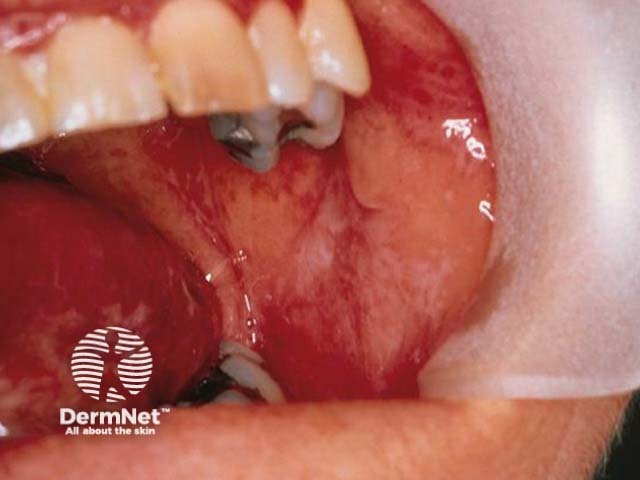

This is oral lichen planus. Note a reticulate pattern of white lines on the buccal mucosa and the lateral side of the tongue.